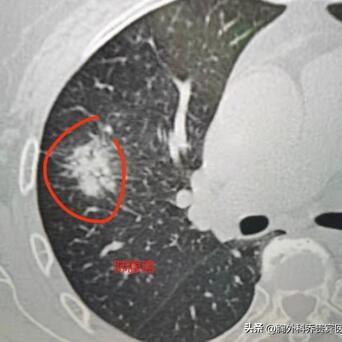

一、肺鳞癌

2、大多数长在肺门附近,中央型肺癌多一些,与吸烟密切相关;

3、扩散方式大多是向周围浸润;